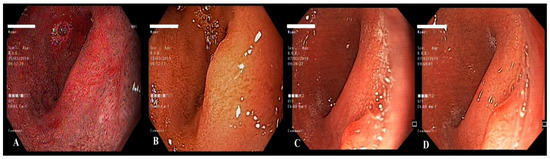

2. Case Report 1